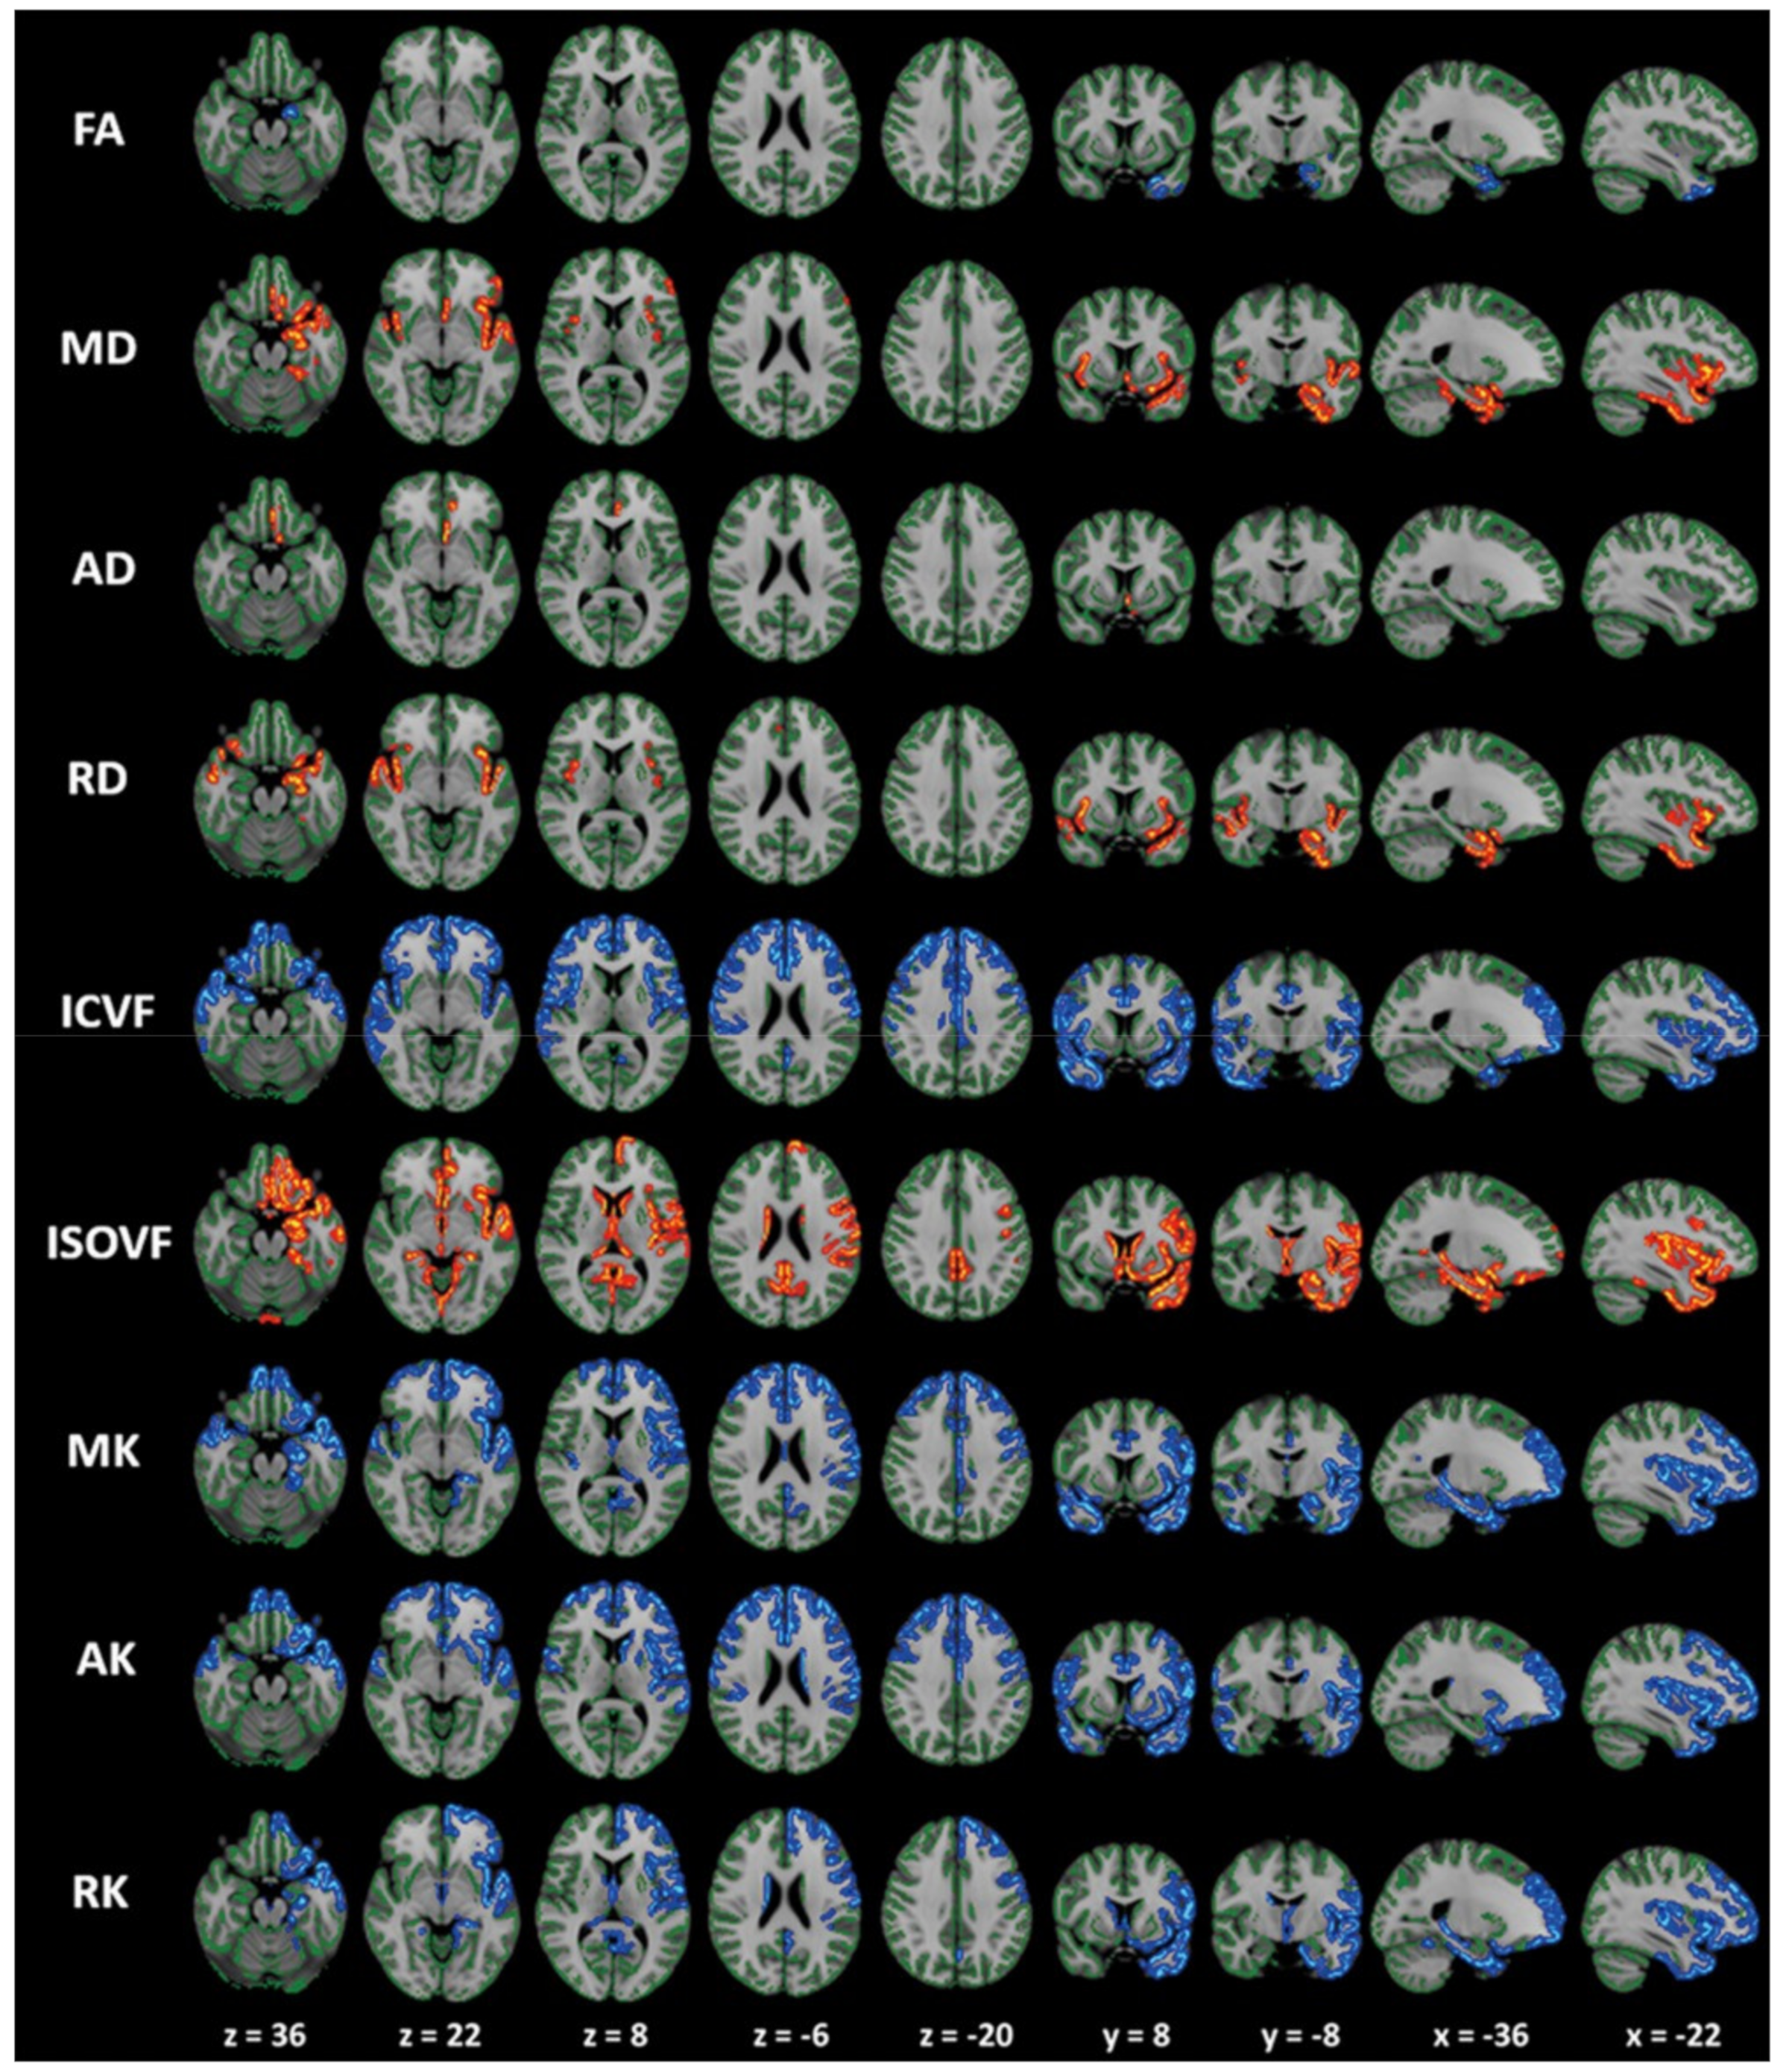

3.3.1. DTI in ALS

3.3.2. DKI in ALS

3.3.3. FWI in ALS

3.3.4. NODDI in ALS